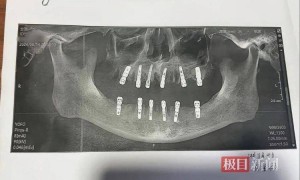

浙江金华一网友近日反映,其父亲8月14日一天内在一家口腔医院拔除23颗牙并种植12颗新牙,之后疼痛不止并去世。9月3日,极目新闻记者了解到,永康市卫生健康局正在调查此事。